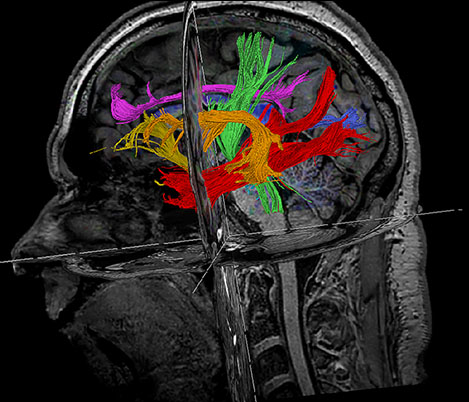

We are continuing with our partners our journey to make MR more accessible1 and definitive2. At ISMRM this year, you will see some more developments that contribute to bringing our vision to life. The need for speed for instance, with Compressed SENSE3, which relies on a heavy sub-sampled acquisition and iterative reconstruction. Come see also our advancements on APT3 (Amide Proton Transfer) a non-contrast technique based on endogenous cellular proteins in tissue, typically present in brain tumors.

APT3 - Non-Contrast technique generating MRI contrast based on endogenous cellular proteins concentration in tissue.